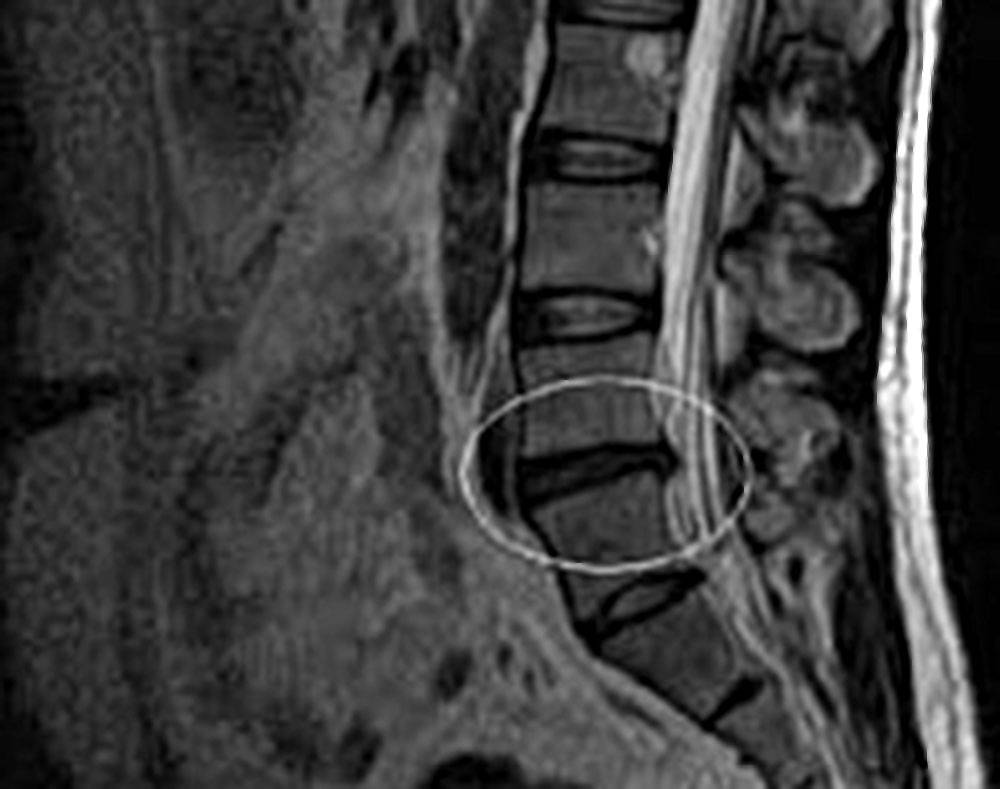

если симптомы, которые есть у пациента, указывают на наличие грыжи, необходим осмотр, инструментально обследование, а также применение ряда диагностических исследований. Полную картину заболевания поможет увидеть МРТ или КТ позвоночника. Эти методы не только помогают визуализировать выпячивание и его точную локализацию, но и дают возможность оценить состояние окружающих тканей, ширину позвоночного канала. Специалист при проведении томографии может менять шаг, с которым производится срез, чтобы попасть в нужную зону. К тому же томография не несет вреда организму и практически не имеет противопоказаний к проведению.

При помощи компьютерной диагностики выявляются также сопутствующие патологии, которые играют роль в дальнейшем лечении грыжи. Если обычная диагностика не дает нужной информации, может применяться обследование с контрастным веществом. Оно назначается редко, так как имеет ряд противопоказаний и может негативно отразиться на здоровье пациента.